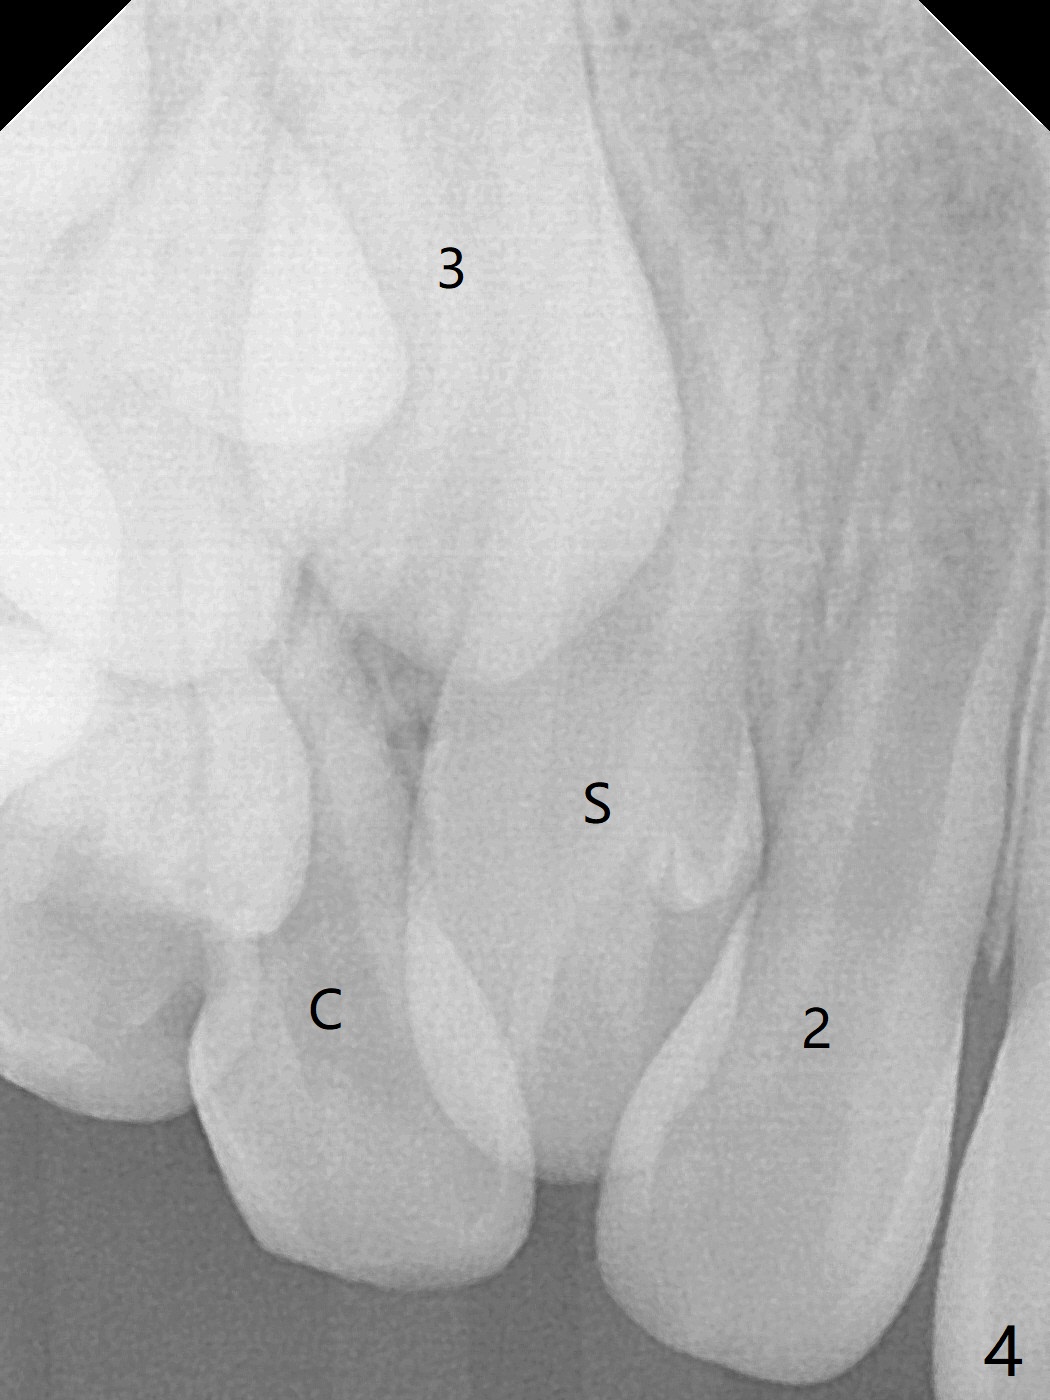

A 6-year-old woman presents to office for limited exam for caries (Fig.1). What was neglected is a super-numerary tooth (S) between UR2 and 3. One year later, the extra tooth appears to be erupting (Fig.2) and linguali-zing UR2 (Fig.3 arrow). PA shows that the extra tooth looks like a lateral (Fig.4). CT will be taken to decide which tooth needs for extrac-tion. The super-numerary tooth (S) blocks UR3 descent, as compared to that of UL3 (Fig.5). The super-numerary tooth with an abnormal cingulum (Fig.6 *) and dens in dente (Fig.6 ^) should be extracted.